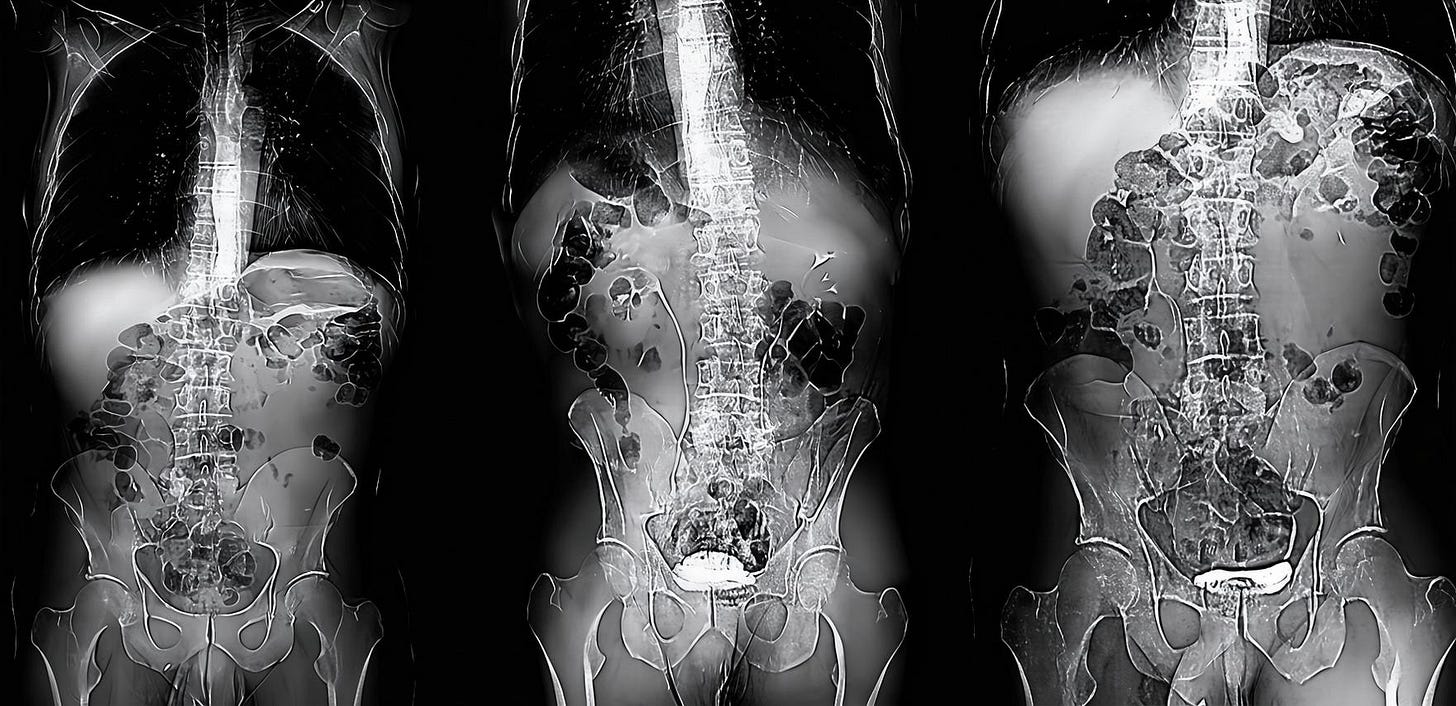

A PET scan is organised a few days later, at St Barts Hospital, in the shadow of St Paul’s. The body is flooded with a tracer radioactive fluid, after which you are locked into a lead-lined box for three-quarters of an hour to allow it to bake in. The scanner then detects where the tracer has been absorbed by cell growth anywhere in the body it is directed, producing reams of flowing light captured to film, copies of which—scans of my own body—are used throughout this post.

On seeing further scans, I recognised, eg., my rib cage as something indeed very much like the frame of Israel’s tents (above, top left), beaming on the shore of the infinite (Blake), but also, in the twisting images of the torso, I am struck by the sprawling energies at play, unleashed by disease. No longer is there the assumed underlying durable person, sealed away from the totality, cybernetically establishing their personal border by fending off and repurposing the chaos, sickness and disorder without. Instead, raw energies start to coalesce, turning Urizenic, mechanical rigidity into flashes, streaks and pulses of contending light.